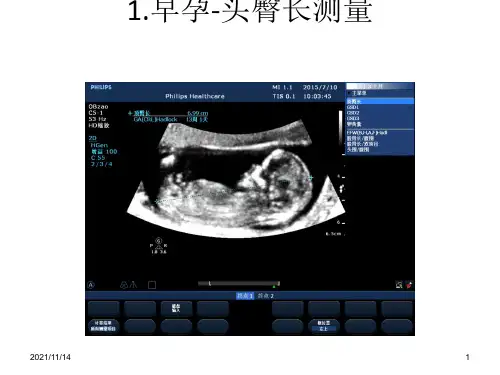

附件3:标准胎儿切面及测量早孕●头臀长测量切面:胎儿正中矢状切面,胎体自然屈曲,头顶及骶尾部清晰显示,躯干部显示脊柱矢状面全长。

放大倍数:放大至胎儿躯体占据屏幕的2/3~3/4。

测量方法:光标置于胎儿头顶皮肤外缘至骶尾部皮肤外缘测量次数:2次测量需全部完成注意事项:入组胎儿首先测量头臀长,如头臀长<45mm,其它项均不需再测量或观察,同时应根据头臀长所对应的超声孕周预约11+0~13+6周的超声检查。

如第一次检查时头臀长>84mm,该病例不入组。